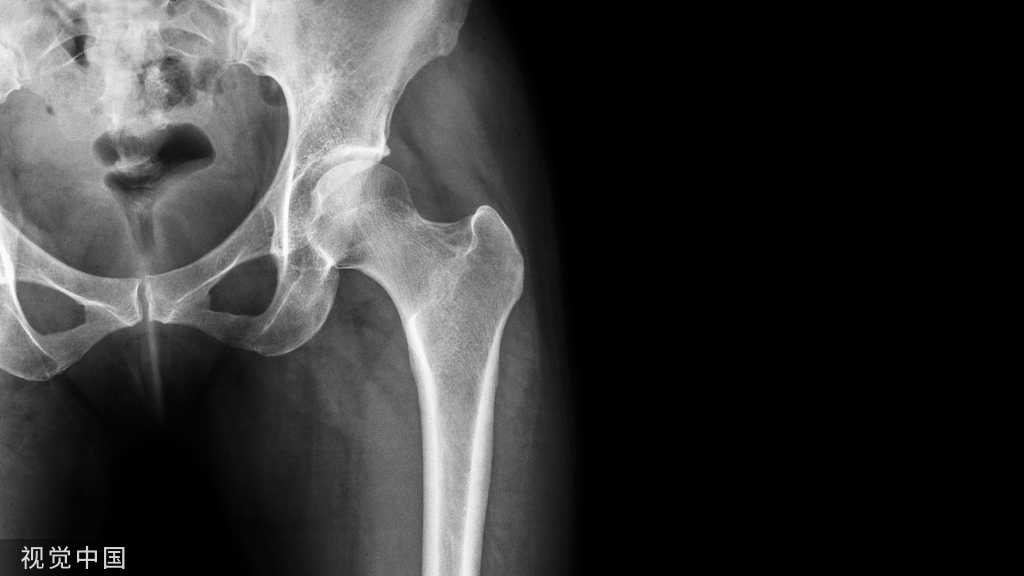

典型病例